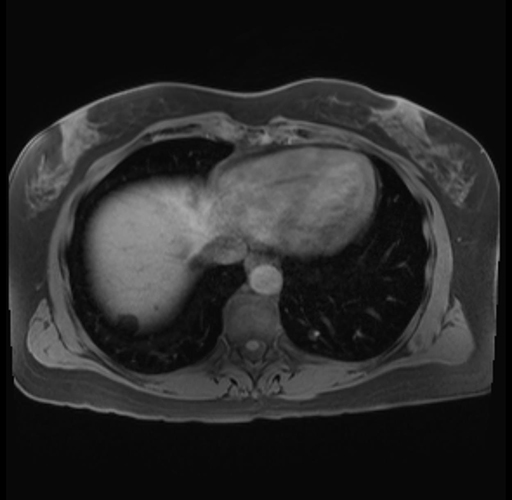

Imaging Analysis

Look through the patient's CT scan to identify any areas of concern for the necessary procedure.

Based on your CT findings, which issue(s) are present and would give reason for "planned slowing down moment(s)" in this case?